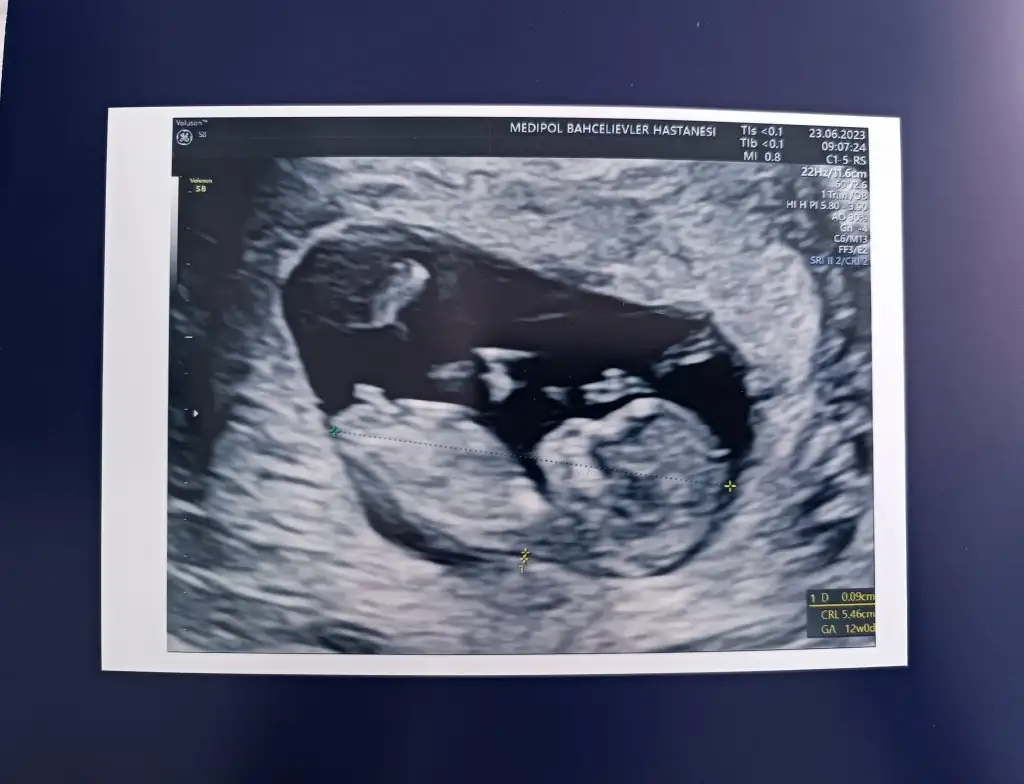

Merhaba teyzoşlarr 12. Haftadaydık ama 4 gün önden gidiyormuşuz 13. Haftadayız. Ve tabiki cinsiyet tahmini yapmadı ikili testi de verdim bakalım hayırlısı, inş hepimizinki sağlıkla gelir.

Merhaba teyzoşlarr 12. Haftadaydık ama 4 gün önden gidiyormuşuz 13. Haftadayız. Ve tabiki cinsiyet tahmini yapmadı ikili testi de verdim bakalım hayırlısı, inş hepimizinki sağlıkla gelir. Eki Görüntüle 3265200